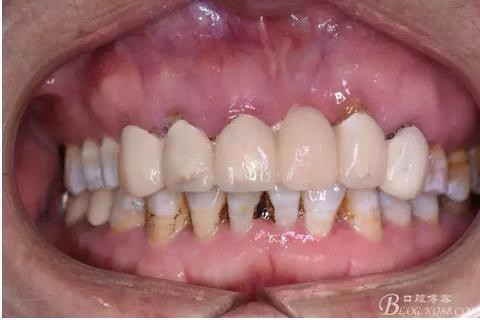

圖3.術(shù)前口內(nèi)正面照:12前庭溝輕度捫痛、有乒乓感